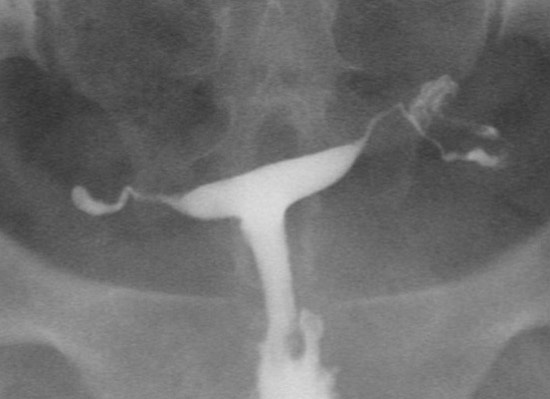

2015년 유럽불임학회(ESHRE) P-769 Almost half of unilateral hydrosalpinx need additional contralateral fallopian tubal surgery (일측 난관수종이 있는 경우, 거의 절반의 경우 반대쪽 난관에 이상이 있어 추가적인 수술이 필요하다.)

When we perform unilateral salpingectomy due to unilateral hydrosalpinx on HSG, is really contralateral fallopian tube normal?

With a unilateral hydrosalpinx on HSG, abnormalities in contralateral fallopian tube were found in 45.6% and performed additional surgeries salpingectomy or fimbrioplasty.

Tubal factor is about one third causes of infertility. For tubal factor evaluation, the most commonly used tests are hysterosalpingography (HSG) and laparoscopy. HSG has high specificity for diagnosis of tubal occlusion and low sensitivity in cases with peritubal adhesions. Tubal patency on HSG does not necessarily indicate normal tubal function. Among women with patent tubes on HSG, 18% were found to have tubal obstruction or peritubal adhesions on laparoscopy.

This retrospective study included 178 salpingectomy cases due to hydrosalpinx on HSG between January 2010 and December 2014.

Total 178 cases salpingectomy were performed. 99 cases were excluded (69 cases - bilateral salpingectomy due to bilateral hydrosalpinx, 30 cases – unilateral salpingectomy due to unilateral hydrosalpinx with contralateral tubal obstruction on HSG/previous salpingectomy).

We analyzed 79 cases with unilateral hydrosalpinx and contralateral normal patency on HSG. Among 79 cases, 43 cases were performed only unilateral salpingectomy (US). 14 cases were performed US and contralateral salpingectomy due to unexpected hydrosalpinx. 22 cases were performed US and contralateral fimbrioplasty or adhesiolysis due to peritubal adhesion or abnormal result on dye test. Therefore in case of unilateral hydrosalpinx on HSG, 45.6% (36/79) were found abnormality of contralateral tube and needed additional surgery.

The subjectivity of radiologists may be involved in interpretation of HSG. Also during operation, the subjectivity of surgeon may be involved in decision making of contralateral tubal surgery.

An abnormal tubal condition affects negatively natural pregnancy or IVF outcomes, therefore proper surgery is needed. Among women with normal tubes on HSG, 18% were found abnormalities on laparoscopy. But with unilateral hydrosalpinx, proportion of requiring opposite fallopian tubal surgery is increased by 45.6%. Therefore, in case of elective unilateral salpingectomy due to unilateral hydrosalpinx on HSG, operators must examine opposite tube carefully and make full explanation about incidental bilateral salpingectomy and possibility of IVF.